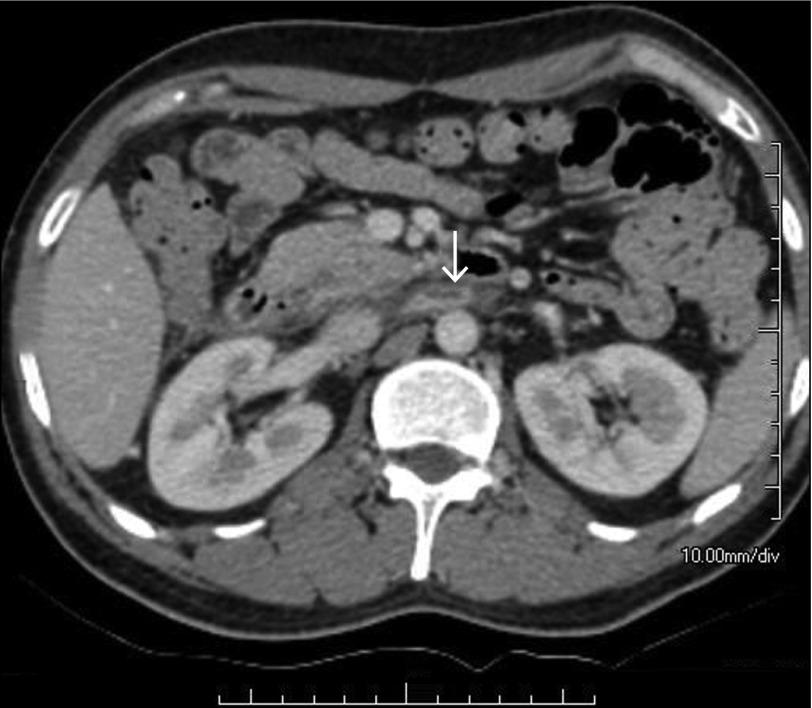

Acute pancreatitis is an inflammatory disorder often associated with various complications. Approximately one fourth of patients with acute pancreatitis develop vascular complications, of which venous thrombosis forms a major group. Extrasplanchnic venous thrombosis is less common, and simultaneous renal vein and inferior vena cava thrombosis is reported only twice. We report a case of alcohol-related acute pancreatitis complicated by simultaneous renal vein and inferior vena cava thrombosis.

急性胰腺炎是一种常伴有各种并发症的炎症性疾病。大约四分之一的急性胰腺炎患者会出现血管并发症,其中静脉血栓形成是主要类型。肝外静脉血栓形成较少见,同时累及肾静脉和下腔静脉的血栓形成仅报道过两例。我们报告一例酒精相关性急性胰腺炎并发肾静脉和下腔静脉同时血栓形成的病例。